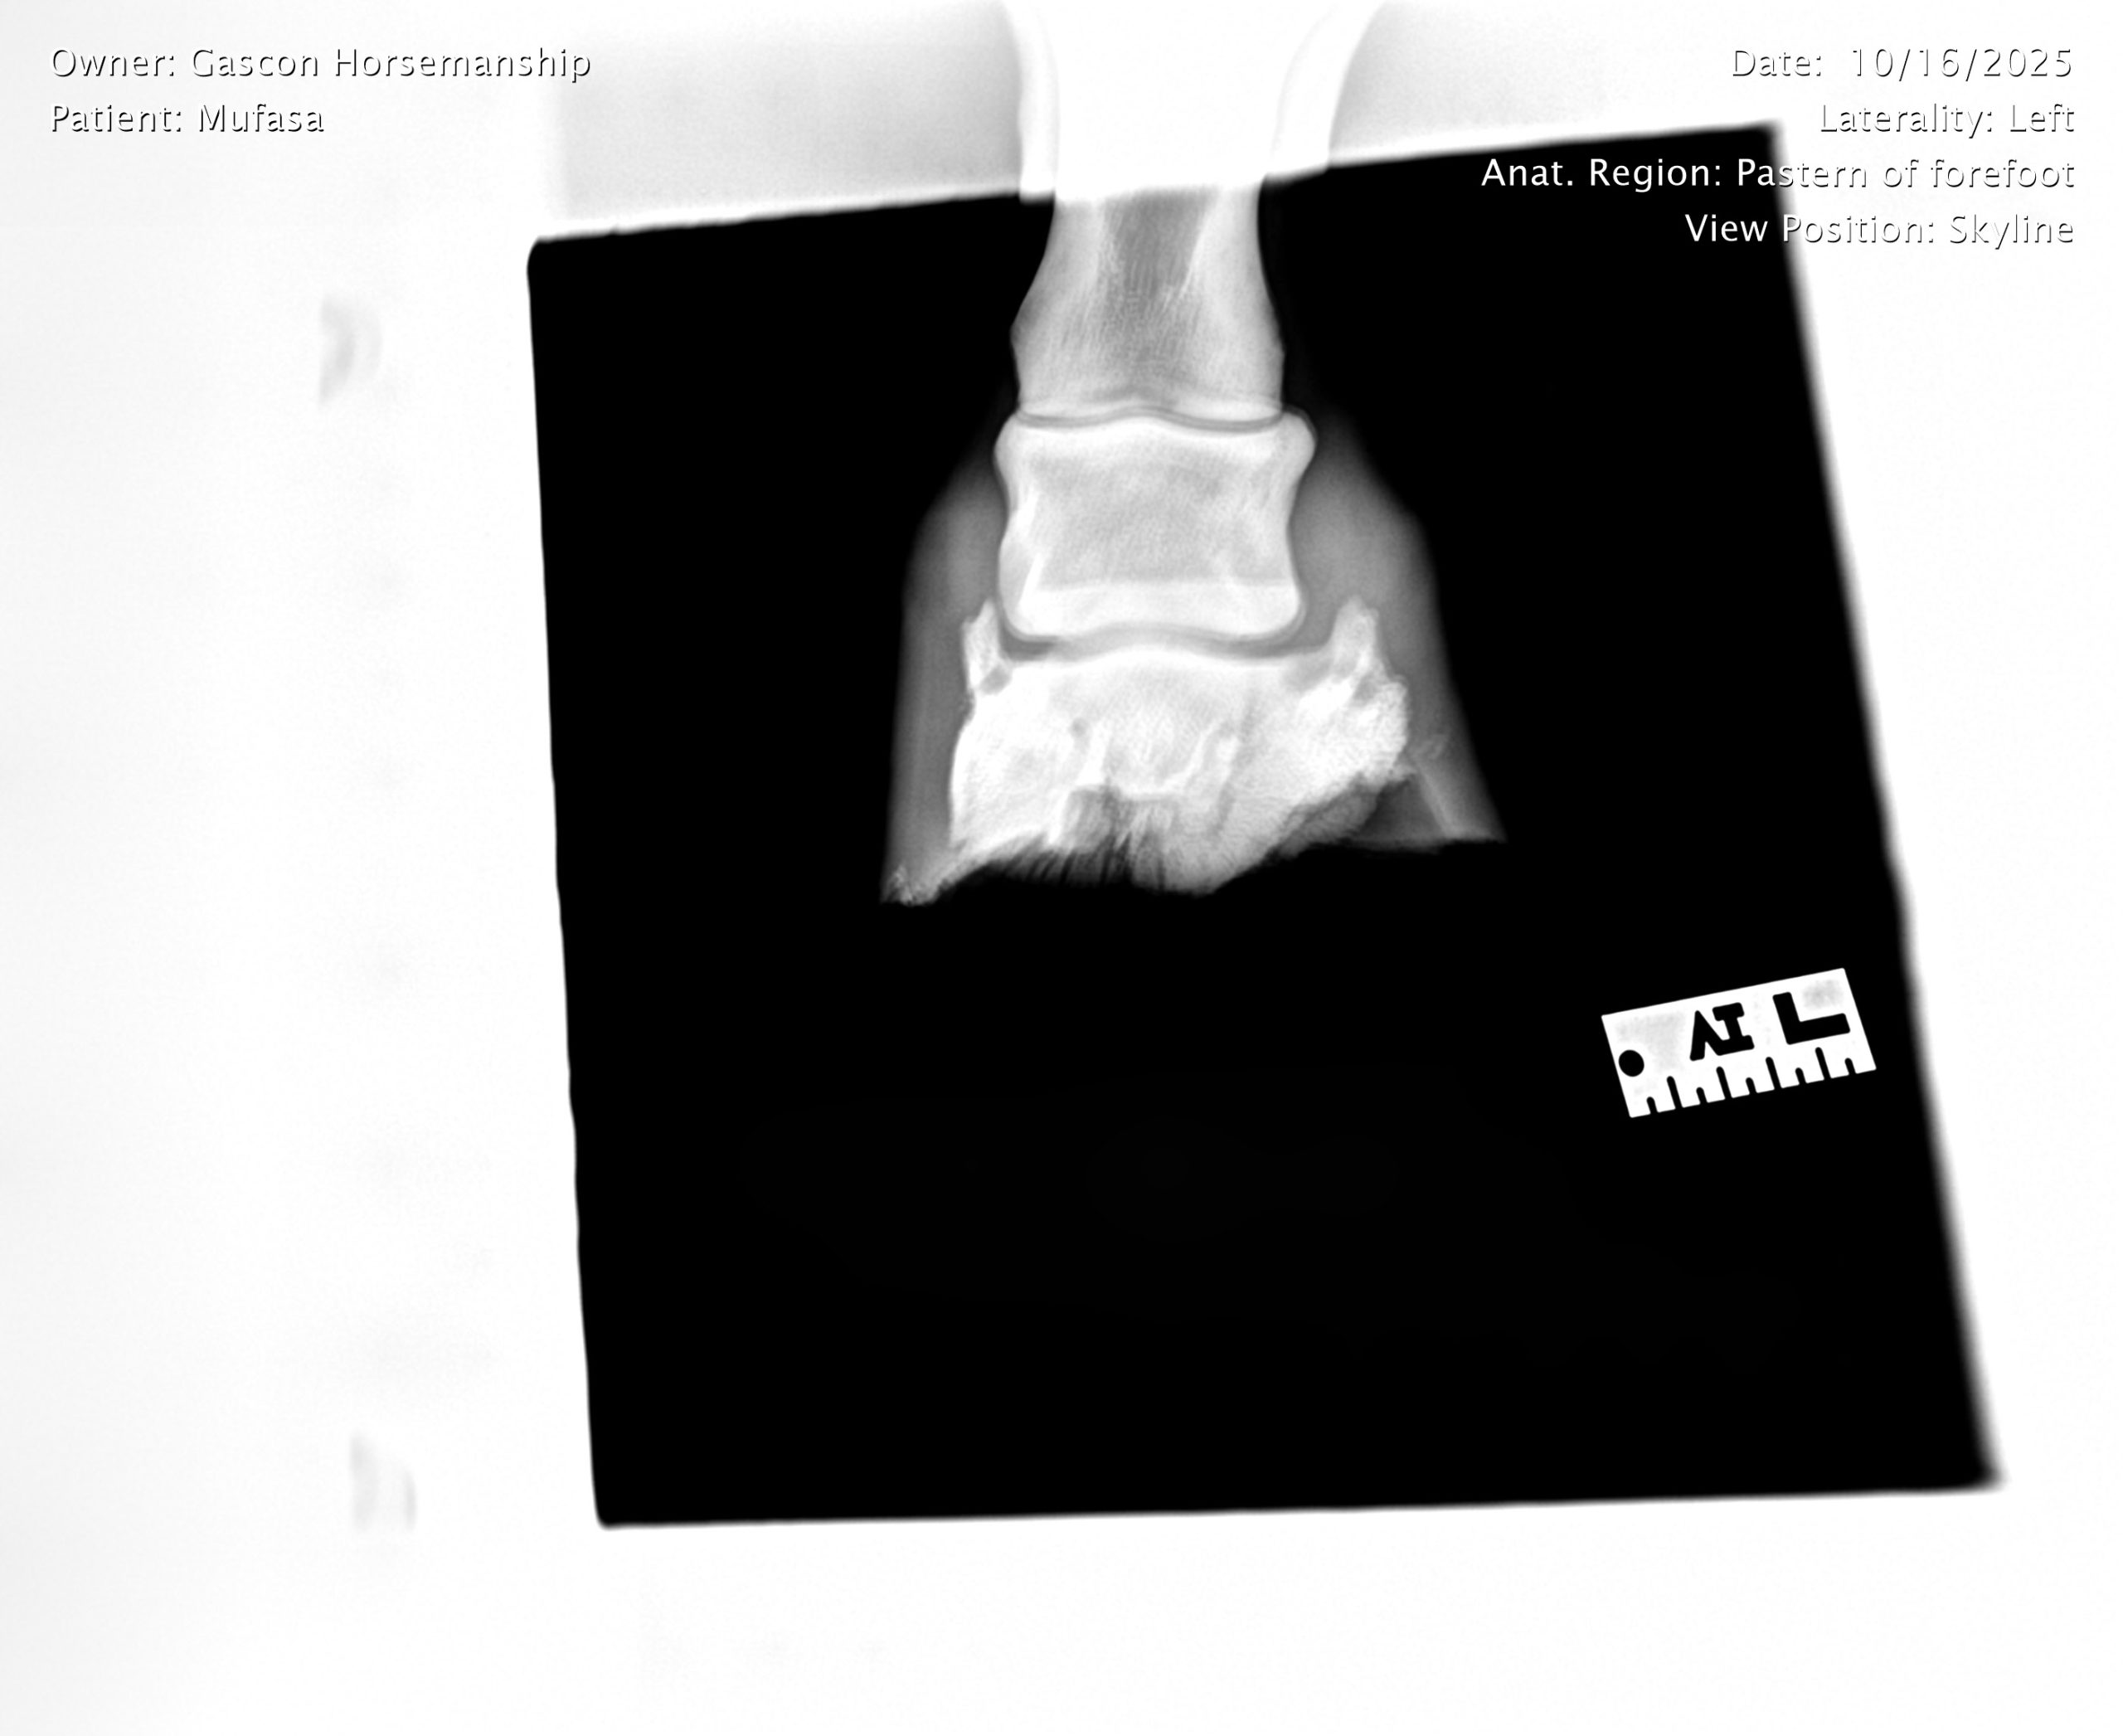

He already has a full pre-purchase exam on file, complete with 25 X-rays included in his album.